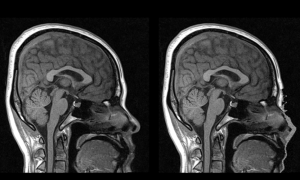

Developed SOP SOP(Standard Operating Procedure) Optical Images EM MR CT EPhys(EEG, MEG) Others Developed SOP SOP(Standard Operating Procedure) Optical Images EM MR CT EPhys(EEG, MEG) Others